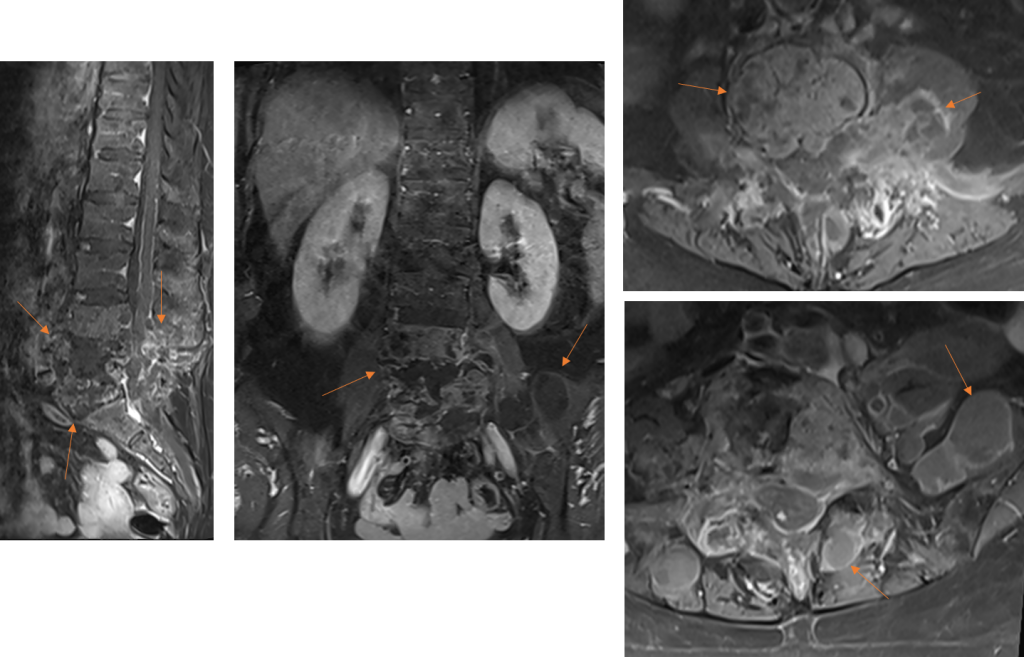

Figura 5: Imagini postcontrast în plan sagital, coronal şi axial. Se remarcă priză de contrast la nivelul pereţilor chistici precum şi la nivelul structurii osoase vertebrale L4 şi L5 din vecinătatea leziunilor chistice (priză de contrast datorată modificărilor edematos-inflamatorii osoase).